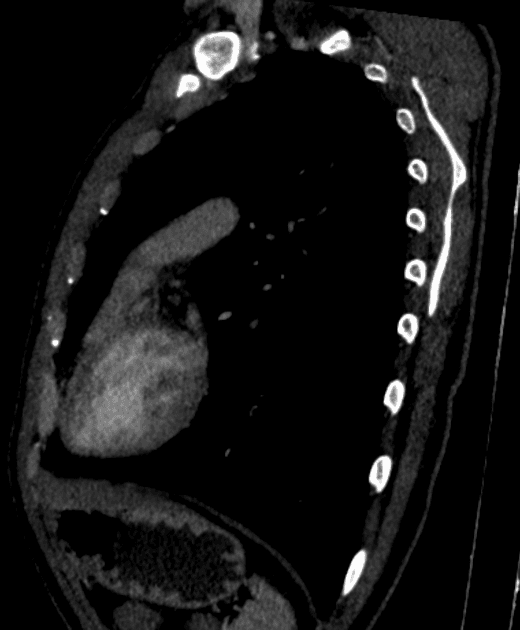

Axial C+ arterial phase

- Hạ sản cung động mạch chủ kéo dài từ đoạn cung xa đến isthmus, với phần còn lại là một kênh liên lạc nhỏ với động mạch chủ xuống.

- Giãn đáng kể thân động mạch phổi với ống động mạch còn thông (PDA) lớn thông nối với động mạch chủ xuống, động mạch chủ xuống nằm ở vị trí bình thường bên trái.

- Các tĩnh mạch phổi được quan sát thấy, có vẻ thông suốt nhưng nhu mỏng.

- Trào ngược thuốc cản quang tại tĩnh mạch chủ dưới (IVC) và các tĩnh mạch gan, liên quan đến thất phải giãn lớn, gợi ý suy tim phải.